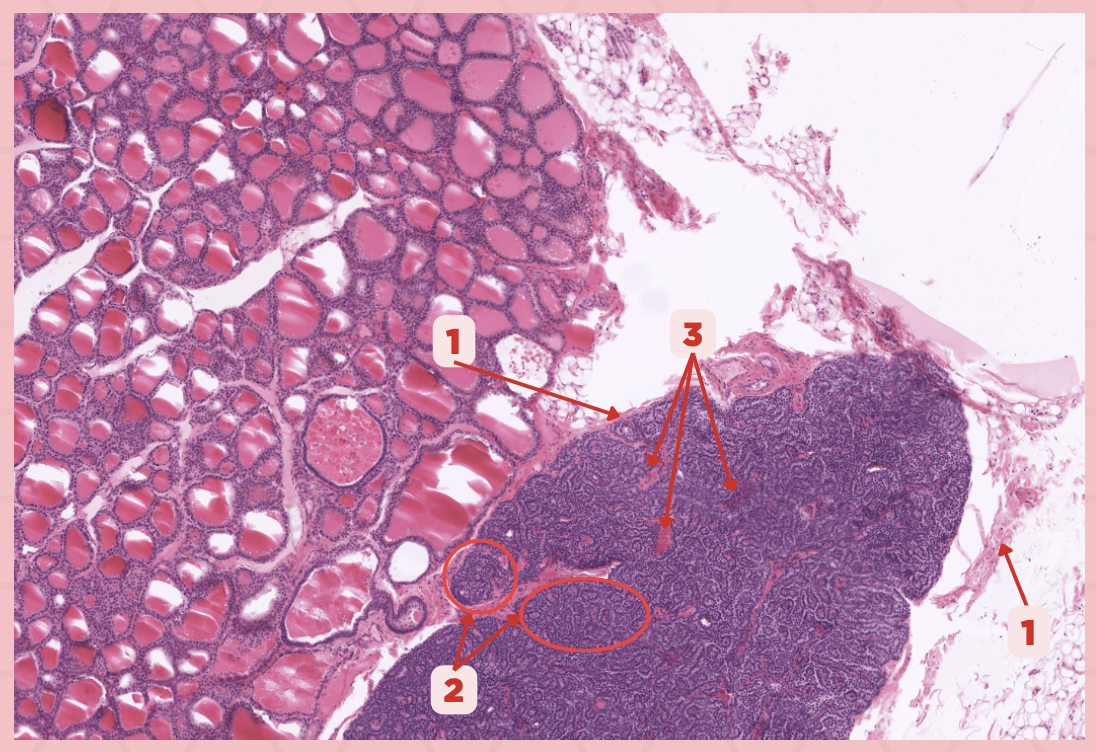

Thyroid-Parathyroid

Identify the specimen.

Thyroid Gland

Identify the structure labeled as 1.

Capsule

Identify the structure labeled as 2 and 4.

Parathyroid Gland

Identify the structure labeled as 3.